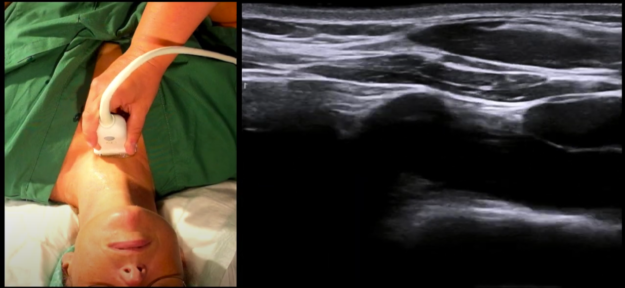

US in eFONA Ultrasound in emergency front-of-neck airway access Nessun anestesista vorrebbe trovarsi nello scenario in cui il paziente non si riesce ad intubare e ad ossigenare (CICO – Cannot…

Di seguito segnaliamo alcuni video didattici su come identificare la membrana cricotiroidea e come eseguire la cricotirotomia Video sull’identificazione ecografica della membrana cricotiroidea: https://youtu.be/0O7F7EVSPGQ https://youtu.be/xGa8m65SoA8?list=PL3qoAYOb9nwy-EN-i-dRFYsO5x4xXDd6T https://youtu.be/Ot61Z5rx1bI Video…